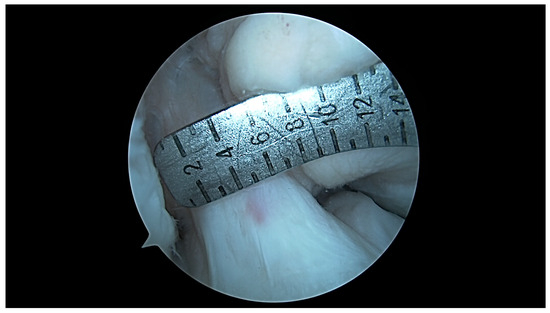

- ICN width: notch width in the distal part